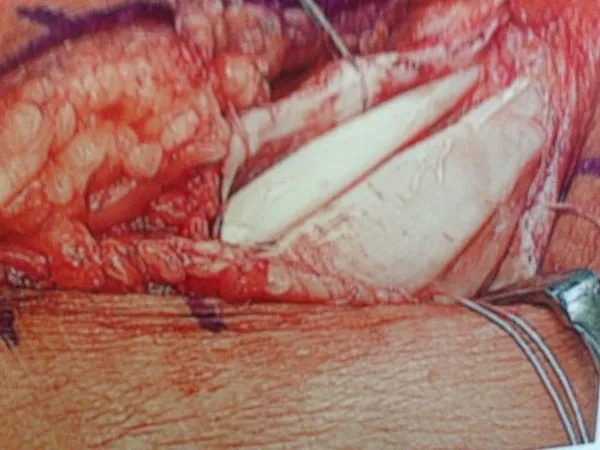

Peroneus Brevis Split Tear with Surgical Repair and Removal of Torn Tendon Portion. (below)

Partial Tear Peroneus Brevis Tendon. (below)

Removal of Torn portion and debulking of tendon. (below)